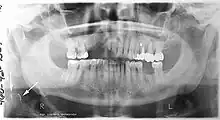

Atherosclerosis is attributed to risk factors that include cigarette smoking, hyperlipidemia, obesity, diabetes mellitus, and hypertension (high blood pressure). These factors, however, do not fully account for the risk of disease. Atherosclerosis has been conceptualized as a chronic inflammatory response to endothelial cell injury[24] and dysfunction possibly arising from chronic dental infection. In 2010, using the previously validated Mattila panoramic radiographic index to quantify the totality of dental infection (i.e., periapical and furcal lesions, pericoronitis sites, carious tooth roots, teeth with pulpal caries, and vertical bony defects), Friedlander's group determined that individuals with carotid artery atheromas on their panoramic radiographs had significantly greater amounts of dental infection/inflammation than atherogenic risk-matched controls devoid of radiographic atheromas.[25][26] While the Mattila index had been previously used to relate the extent of dental infection to coronary artery disease, this research is the first to link the full range of dental disease that it measures to panoramic radiographs evidencing calcified carotid artery atherosclerosis.